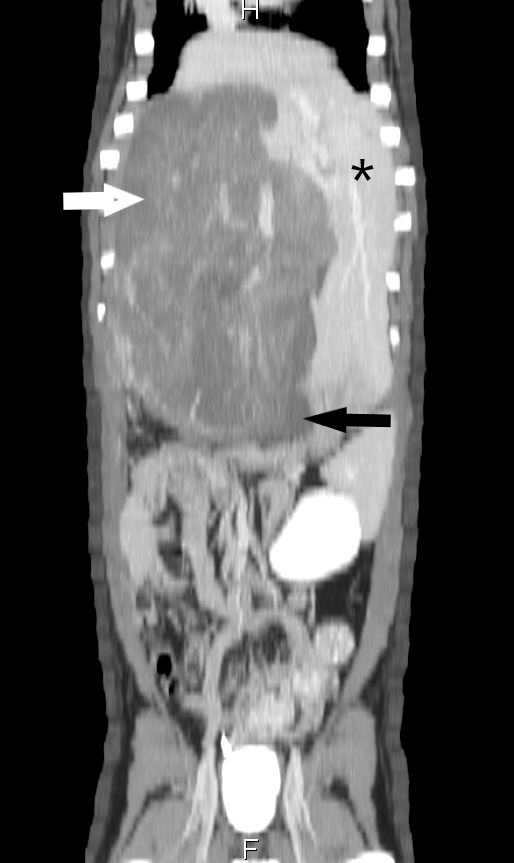

A contrast CT angiogram was then performed showing a very large mass arising from the right medial liver lobe compressing the gall bladder and adjacent caudal vena cava. A representative picture of the CT scan performed here at AVES is shown to the right with the white arrow indicating the mass, asterisk showing normal liver, and black arrow showing the compressed gallbladder..